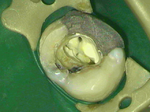

The Dental Microscope provides the dentist with unprecedented vision.

If more complicated care is required such as crowns or root canal treatment, we can provide this with improved accuracy and optimise the treatment.

The microscope has an integrated medical grade video camera so we can demonstrate live images to explain treatment decisions.